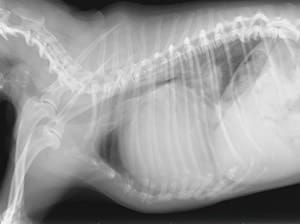

レントゲン検査

心臓の大きさや形の検査、さらに気管や肺の状態もチェックいたします。